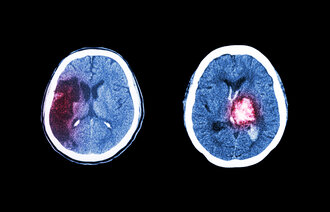

Hjerneslag rammer omtrent 12 000 personer hvert år. Hjerneslag oppstår plutselig og kan skyldes en blodpropp eller en blødning i hjernen (1). Etter hjerneslag kan pasienter få utfordringer med talen eller med sin fysiske, kognitive og/eller sosiale funksjon. Rehabiliteringsprosessen tilpasses hver enkelt pasients utfordringer og behov.